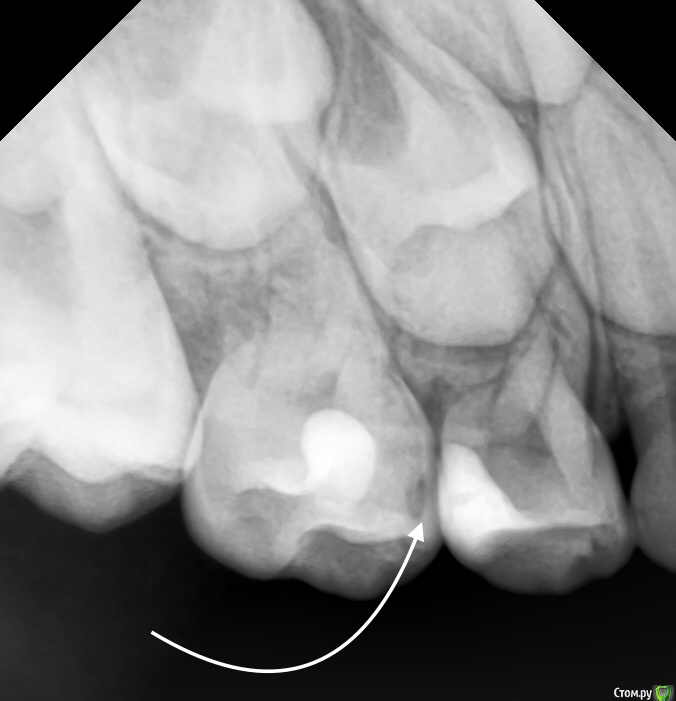

CRAZYDUCK Опубликовано 14 июня, 2018 Автор Поделиться Опубликовано 14 июня, 2018 Очередная история про скрытый кариес . Все зубы пролечили и успокоились . Пропали на год -два . А кариес растёт и радуется . Коллеги ,часто так бывает ? Часто . Но не в этом случае . Осмотр спустя 7 месяцев помог выявить скрытую кариозную полость на 5.5 зубе . RVG ( хочу diagnocam Ссылка на комментарий